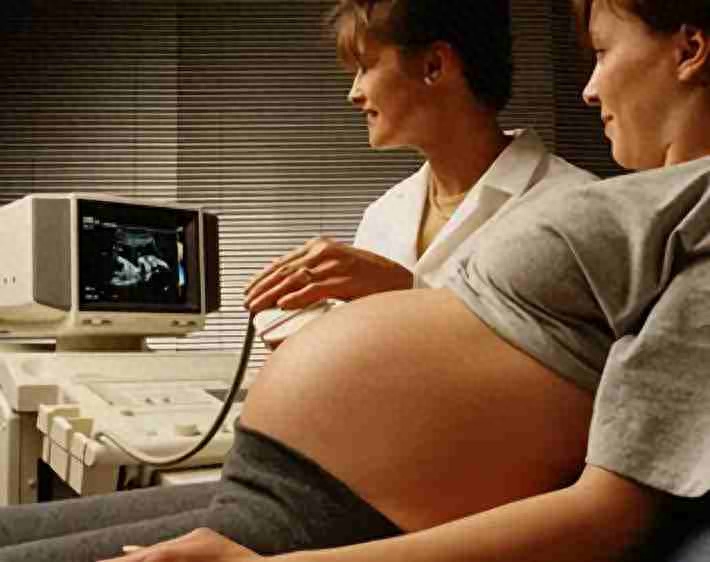

B型:用平面图形的形式来显示被探查组织的具体情况。检查时,首先将人体界面的反射信号转变为强弱不同的光点,这些光点可通过荧光屏显现出来,这种方法直观性好,重复性强,可供前后对比,所以广泛用于妇产科、泌尿、消化及心血管等系统疾病的诊断。

B型超声探测仪

孕检时要做的B超